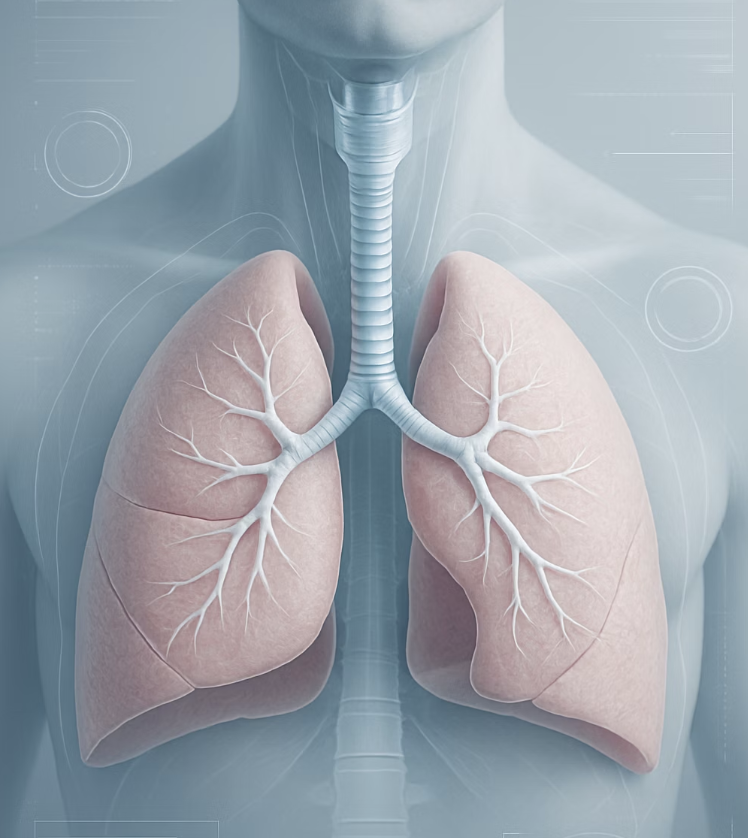

숨 쉴 때마다 아프다면, 폐의 목소리

우리 가슴 안에는 심장과 함께 ‘폐’가 큰 자리를 차지하고 있습니다. 오른쪽 폐를 둘러싸고 있는 얇은 막(흉막)에 염증이 생기는 ‘늑막염’이나, 폐렴이 심해져 흉막까지 염증이 번졌을 때 오른쪽 가슴에 통증이 나타날 수 있습니다. 또한, 드물게는 폐에 구멍이 뚫리는 ‘기흉’이 원인이 되기도 합니다.

폐와 관련된 통증의 가장 뚜렷한 특징은 ‘호흡’과 직접적인 연관이 있다는 점입니다. 숨을 깊게 들이마시거나 기침, 재채기를 할 때 칼로 찌르는 듯한 날카로운 통증이 느껴진다면 폐의 이상을 의심해 볼 수 있습니다. 만약 가슴의 불편함과 함께 심한 기침이나 가래, 고열이나 호흡 곤란이 동반된다면 지체 없이 병원을 찾아 진료를 받아야 합니다.